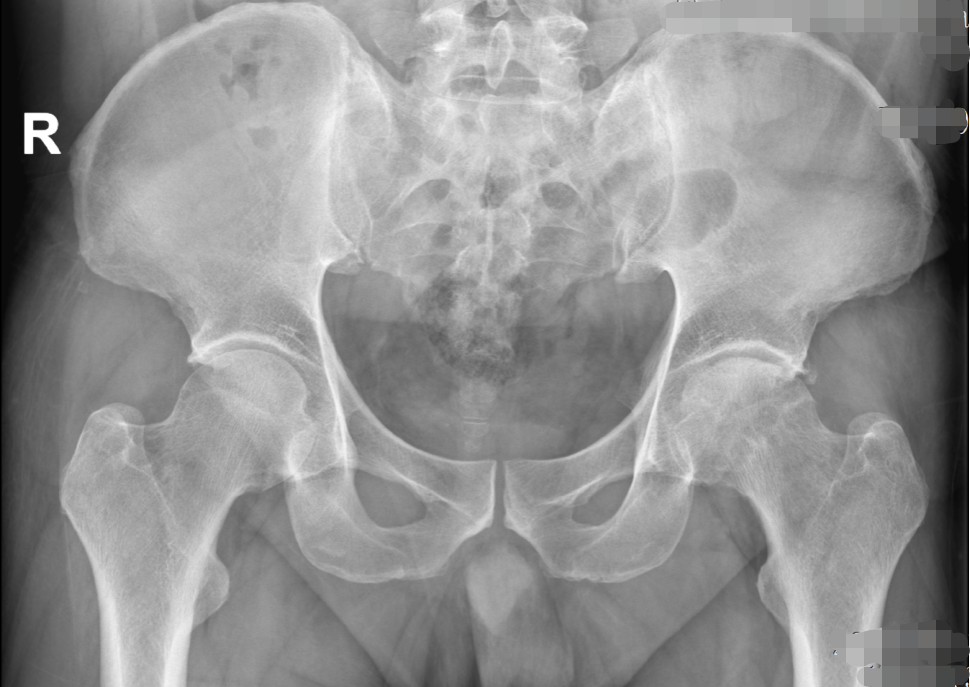

经胡舒主任详细检查,吴先生确诊为左侧股骨头缺血性坏死(三期)。由于保守治疗效果不佳,为有效改善功能、缓解症状,胡舒主任建议进行全髋关节置换。在充分沟通和了解了自己的疾病及治疗方式后,吴先生选择在家门口的东凤人民医院手术治疗,方便了家人护理和后续自己的定期复诊。

术前(骨盆正位)                                                                                                                           术后(骨盆正位)